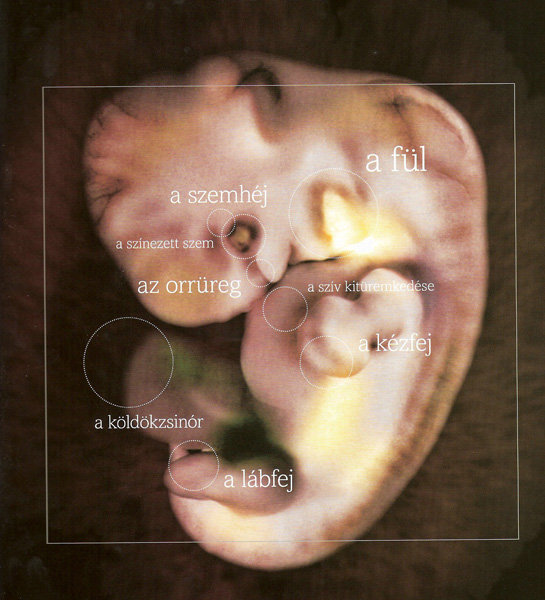

Annus nagyon jók a képek. kis ALien-nek néznek ki... szép az élet...

Annus, nem lehet, hogy a képen, amin 7. hét van. az a 7. terhességi héten készült, és nem a mensitől számítva, mert a táblázat szerint, amit a babanet küldnekem hetente az áll, hogy a 7 hét végén lesz kb 10 mm.

5mm a baba

5mm a baba  8 mm a baba

8 mm a baba  11 mm a baba

11 mm a baba  18 mm a baba

18 mm a baba

30 mm a baba

30 mm a baba Bébike nagyításban és életnagyságban

Bébike nagyításban és életnagyságban